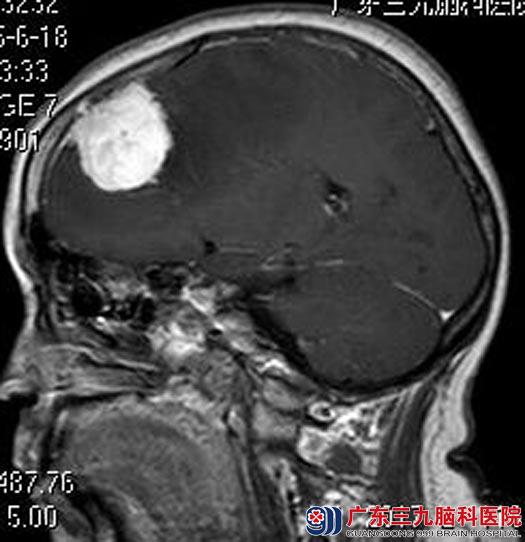

情急之下,一家人想到了广东三九脑科医院。进一步头颅MR检查提示:左侧额部大脑凸面示一团块状异常信号影,大小约37.9mm×37.2mm×38.9mm,增强后较均匀明显强化,并示脑膜尾征,内侧紧邻大脑镰,局部压迫上矢状窦,考虑左侧额部大脑凸面脑膜瘤可能,待排除血管外皮细胞瘤可能。